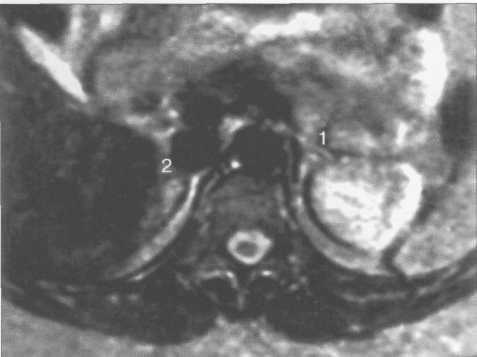

Нормальные надпочечники на Т1- и Т2-ВИ представляют собой однородные, гипоинтен-сивные структуры, которые хорошо дифференцируются на фоне окружающей жировой клетчатки (рис. 12.7). При использовании Т2-В И сигнал от паренхимы надпочечников сравним с таковым от паравертебральных мышц; незначительно превышает сигнал от печени и коркового вещества почек и значительно превосходит сигнал от ножек диафрагмы (рис. 12.8).

Рис. 12.8. МРТ надпочечников. Т2-ВИ, аксиальная плоскость.

1 — левый надпочечник; 2 — правый надпочечник.